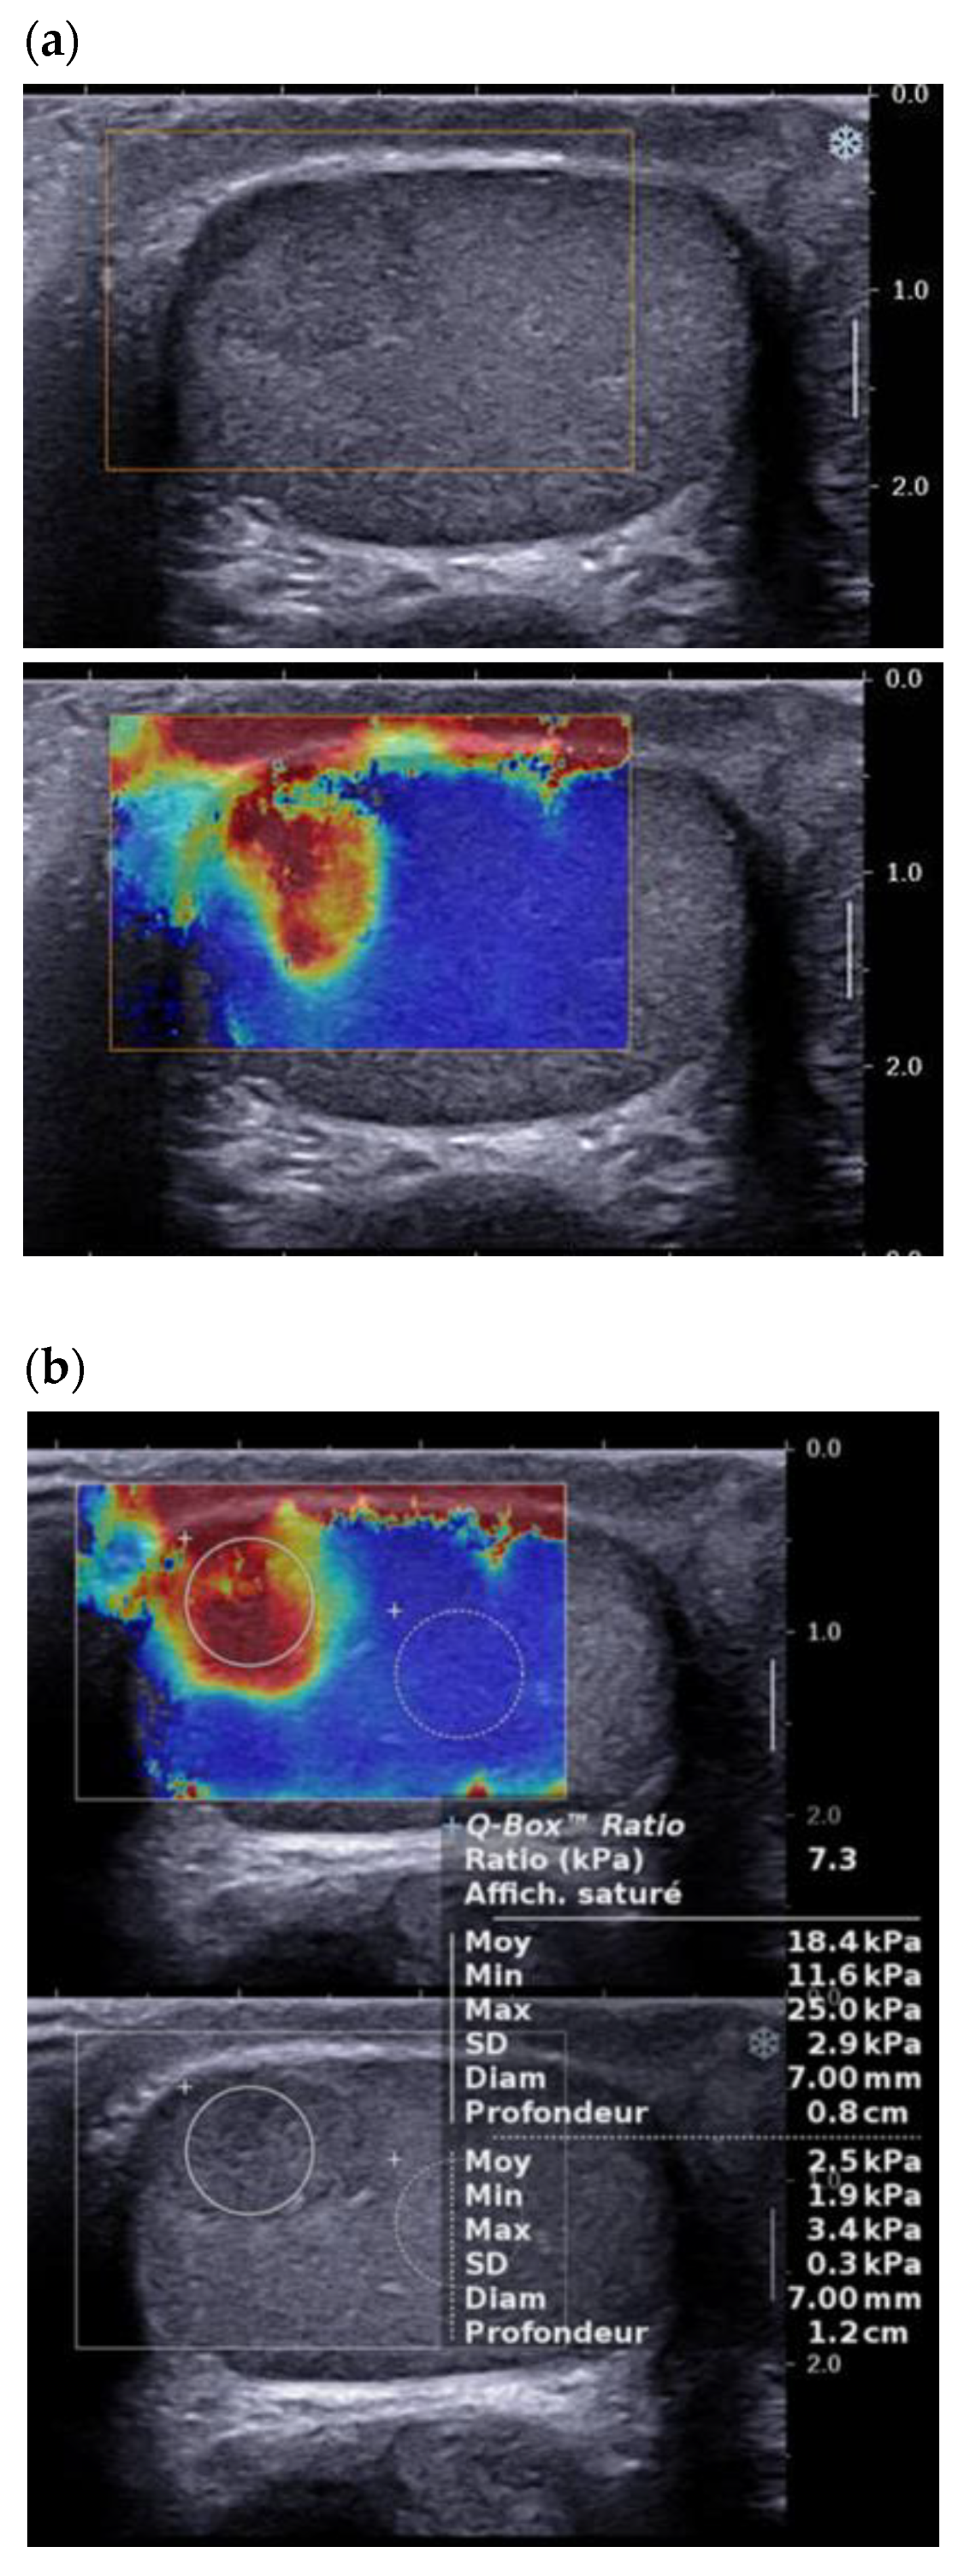

3.4. Elastography

The PubMed search using the key words Leydig cell tumour/tumor—ultrasound/sonography—elastography—SWE—strain elastography—SE—shear wave yielded 8 references between 2012 and 2021, including 2 case reports.

The use of testicular elastography spread at the end of the 2000s. Most studies use the technique of strain elastography. In 2012, Goddi et al. reported promising results, with a sensitivity/specificity of 87.5%/98.2% in differentiating benign lesions from malignant lesions, though this study included only 2 LCTs among the 103 nodules studied [22]. The first prospective study to include a significant number of LCTs was that of Pozza et al., who studied 106 testicular lesions, 20 of which were LCTs, using strain elastography with a visual scale for stiffness and an analysis of the lesion/healthy parenchyma stiffness ratio [23]. This classification allowed differentiation between tumor lesions and non-tumor lesions, but showed an overlap (visual scale and stiffness ratio) between malignant and benign tumors (including 52% of proven LCTs). More recently, Konstatatou et al. in a retrospective study of 86 lesions, including 12 histologically proven LCTs, showed that the stiffness ratio outperformed the visual scale in differentiating malignant lesions from non-tumor lesions, but no significant difference allowed discrimination between tumor lesions [24]. Shear wave elastography enables quantitative analysis of lesion stiffness. Roy et al. reported quantitative data of median stiffness: 4.55 kPA for healthy testicular parenchyma, 21 kPA for tumor lesions and 30 kPa for fibrosis, but this study excluded LCTs from the analysis [25]. Rocher et al. analyzed 86 testicular lesions, including 28 LCTs, 37 malignant tumors, and 12 burned-out tumors. Shear wave elastography distinguished the LCTs from malignant tumors and burned-out tumors, with an area under the curve of 98% [24,25]. Overall, the convergent literature data show that LCTs, like other tumor lesions, have greater stiffness than the adjacent parenchyma (Figure 5). However, most studies included very small numbers of LCTs, and only Rocher et al. have shown a statistically significant difference between LCTs and malignant lesions (seminomas, non seminomatous germ cell tumors, burned-out lesions) [26].

Figure 5.

Same patient as Figure 1: Shear wave elastography of typical LCT, qualitative (a) and quantitative (b) evaluation of stiffness.